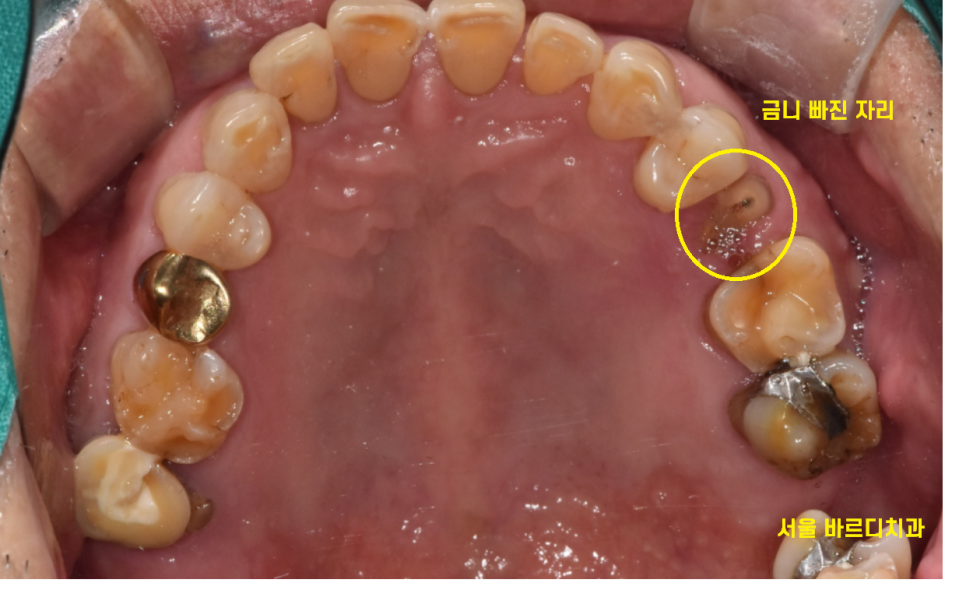

금니 빠짐 부위가 치아와 함께

부러졌네요ㅠㅠ

충치가 없고 깨끗하면 그대로 붙이고

보철물에 변형이 생겼거나

충치가 있을 경우 다시 새로 만들고

오늘 환자분처럼 완전히 부러지면...

미사 임플란트를 진행하여야합니다.